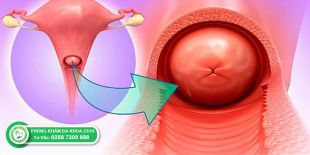

Áp lạnh cổ tử cung là một trong những phương pháp hiện đại được ứng dụng trong điều trị viêm lộ tuyến cổ tử...

Phì đại cổ tử cung là biểu hiện của viêm nhiễm ở vùng cổ tử cung kéo dài. Đây là một trong những bệnh lý phụ khoa...

Viêm cổ tử cung là một trong những căn bệnh phụ khoa phổ biến dễ gặp ở nữ giới do các tác nhân có hại như vi khuẩn...